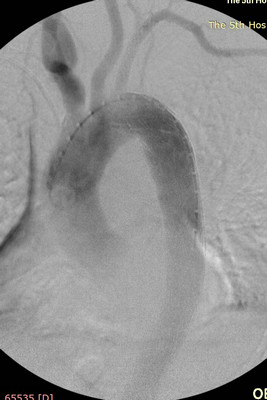

充分的术前评估及准备,确保了手术的顺利进行。术中王兵教授亲自主刀,崔文军副主任及王颖、司江涛主治医师作为助手,经股动脉小切口,先于左侧锁骨下动脉狭窄处准确定位后置入球扩支架1枚,再次造影明确溃疡位置后,将主动脉带膜支架顺利输送到位,并成功释放,完全覆盖病变主动脉,复查造影效果满意(图3)。术后患者即清醒,安全返回病房,测量双上肢血压无差别,双下肢温度、颜色正常,感觉及运动均无异常,即挽救了患者生命,也成功避免了截瘫的发生,大家悬着的心都放了下来。术后施敏护士长带领的护理团队,娴熟而全面的护理确保患者平稳度过围手术期,术后10天复查CTA:左侧锁骨下动脉及主动脉支架均位置良好,形态满意。目前李大娘已顺利康复出院。

图3:术中支架释放后造影 图4:术后10天复查CTA